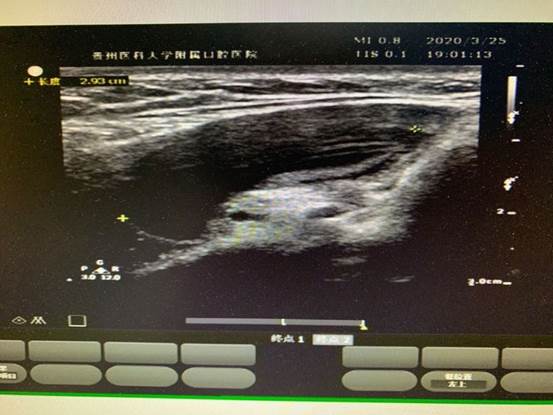

疫情以来,心电图室及超声室每一位医护人员都认真学习疫情防控方案、要求,遵循医院的安排,心电图室根据患者需求科学排班,24小时随时待命。多次夜间急诊、周末节假日出诊,心电图室积极配合,第一时间为患者行床旁心电图,及时解决一线的燃眉之急;超声室共接诊病人36人次,其中多以颌面部包块病人为主,并积极配合口外医生实施手术及穿刺,在与临床医生配合下,确诊了两例舌下腺囊肿(口外型)病人,一例已手术。